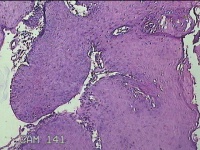

口腔黏膜肿物

性别

男

年龄

6岁

临床诊断

口腔黏膜粘液囊肿

一般病史

右下唇部一月余。

标本名称

大体所见

灰白粉红色囊性肿物0.7x0.5x0.3cm一个,表面光滑。

图2

良性病变。